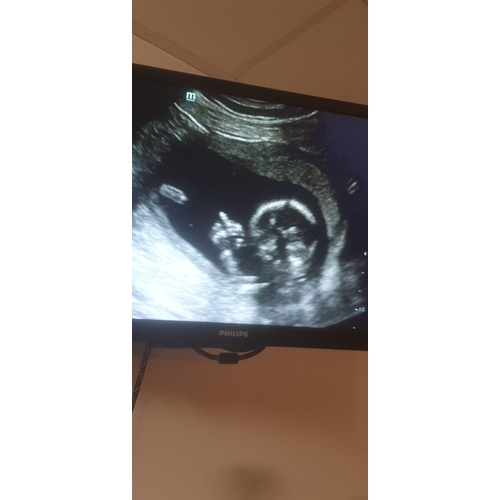

Gezichtje vanaf de voorkant. Was net zo'n porseleine horror pop😅

Ik moest even goed kijken, maar ik zie het ja! Inderdaad griezelig zo